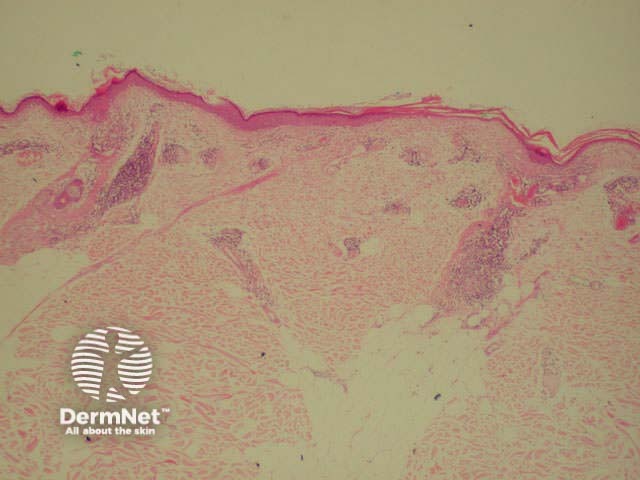

Dermatopathological findings in SLE include a lichenoid tissue reaction and a band of immunoglobulins at the dermo-epidermal junction (detected by direct immunofluorescence of clinically involved skin).

Dermatopathology of systemic lupus erythematosus This shows a dense perivascular and periadnexal lymphocytic inflammatory infiltrate and interface changes with vacuolar degeneration of basal layer

Low power view